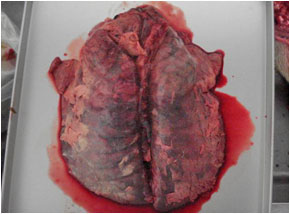

剖検:

- (1)肝の腫脹と小白色壊死斑の散在

- (2)脾腫